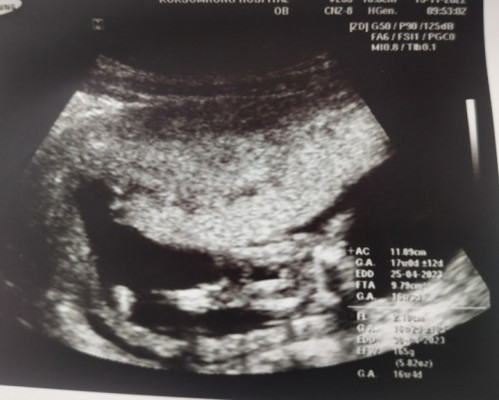

แม่แม่ช่วยดูหน่อยค่ะหมอบอกเป็น ผญ. แม่ๆคิดว่าจะมีการเปลี่ยนมั้ยคะ อยากได้ ผญ.มากค่ะลุ้นว่าอย่าเปลี่ยนเลย😂😂

เรามองว่าผู้หญิงนะ มาเป็นกลีบเลยแม่ บ้านนี้14w แล้ว ลุ้นเพศมากๆ อยากได้ผู้หญิง🤣

อันนี้จากที่หมอลงความเห็นมาในสมุดสีชมพูค่ะ ภาพอัลตร้าซาวด์น้องอยู่ท่าเอียงข้างค่ะ